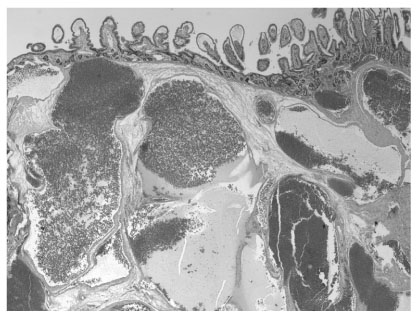

Fig. 3

Microscopic examination of the hemangioma, showing large, dilated, blood-filled vessels lined by flattened endothelium and focal thickening of the vascular walls by adventitial fibrosis (H & E, × 20 original magnification).

Fig. 3 Microscopic examination of the hemangioma, showing large, dilated, blood-filled vessels lined by flattened endothelium and focal thickening of the vascular walls by adventitial fibrosis (H & E, × 20 original magnification).